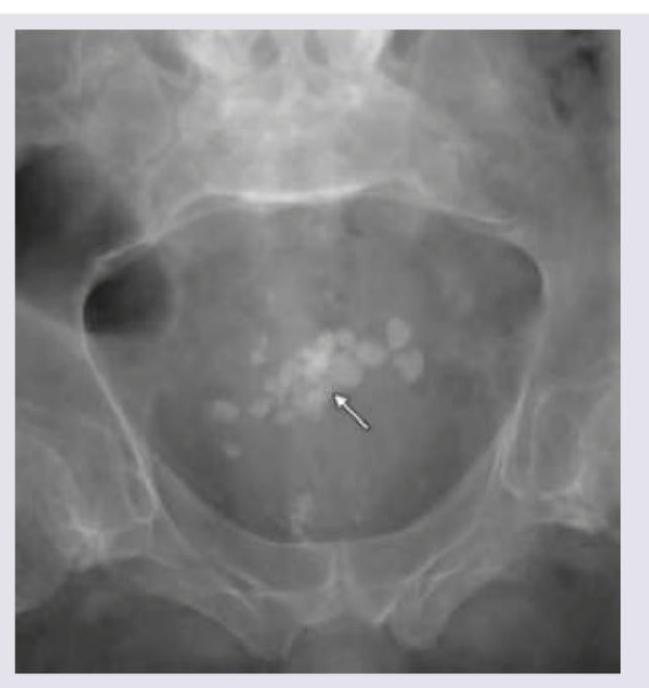

The following image shows the presence of?

Explanation: ***Bladder stone*** - The image displays multiple **radiopaque densities** (stones) clustered within the pelvic cavity, specifically in the region where the urinary bladder is anatomically located. - The aggregation and rounded shapes are characteristic of **vesical calculi** (bladder stones). *Ureter stone* - **Ureteral stones** would typically appear as a single or a few stones following the course of the ureters, which are tubular structures extending from the kidneys to the bladder. - The diffuse, multi-focal collection seen in the image is not consistent with the typical presentation of a ureteric calculus. *Urethral stone* - A **urethral stone** would be located within the urethra, which is inferior to the bladder and would typically present as a single, elongated calculus in the distal urinary tract. - The location and multiple, scattered appearance in the image do not match a urethral stone. *Prostate calcification* - **Prostatic calcifications** are usually smaller, often punctate, and concentrated within the confines of the prostatic gland, typically inferior to the bladder neck. - The calcifications in the image are larger and more widely distributed, not confined to the typical anatomical borders of the prostate.